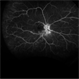

- A 45-year-old female presented with complaints of gradual loss of vision before 3 months and when reached to hospital had this picture.